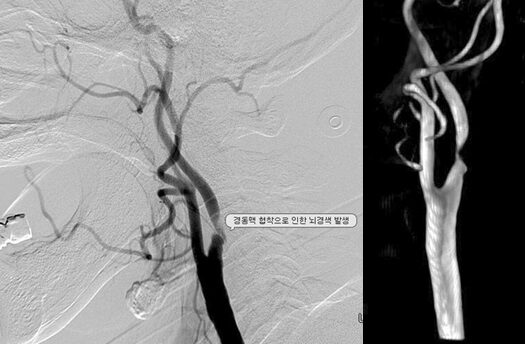

<출처 : 생로병사의 비밀 , 뇌졸증의 적신호, 경동맥협착증>

경동맥협착증의 증상은?

경동맥 협착증이 있을경우 가볍게는 어지러움을느낄 수 있으며, 뒷목이뻣뻣한 느낌을 받을수있습니다. 심할 경우 안면마비나사지마비, 이상 감각, 인지기능 장애, 신경정신과적인증상이 발생할 수있습니다. 때때로 식물 상태내지 사망에까지 이를수 있는 무서운질환이므로, 경동맥협착증이의심될 때는 정확한진단을 받아보는 것이좋습니다.

경동맥협착증 검사는?

경동맥협착증검사는초음파를 이용한 검사가가장 안전하고 정확합니다.

경동맥초음파검사는목부위에서 뇌로 이어진혈관인 경동맥의 좁아진정도나

혈류가 제대로가는지를 확인하는 검사입니다.